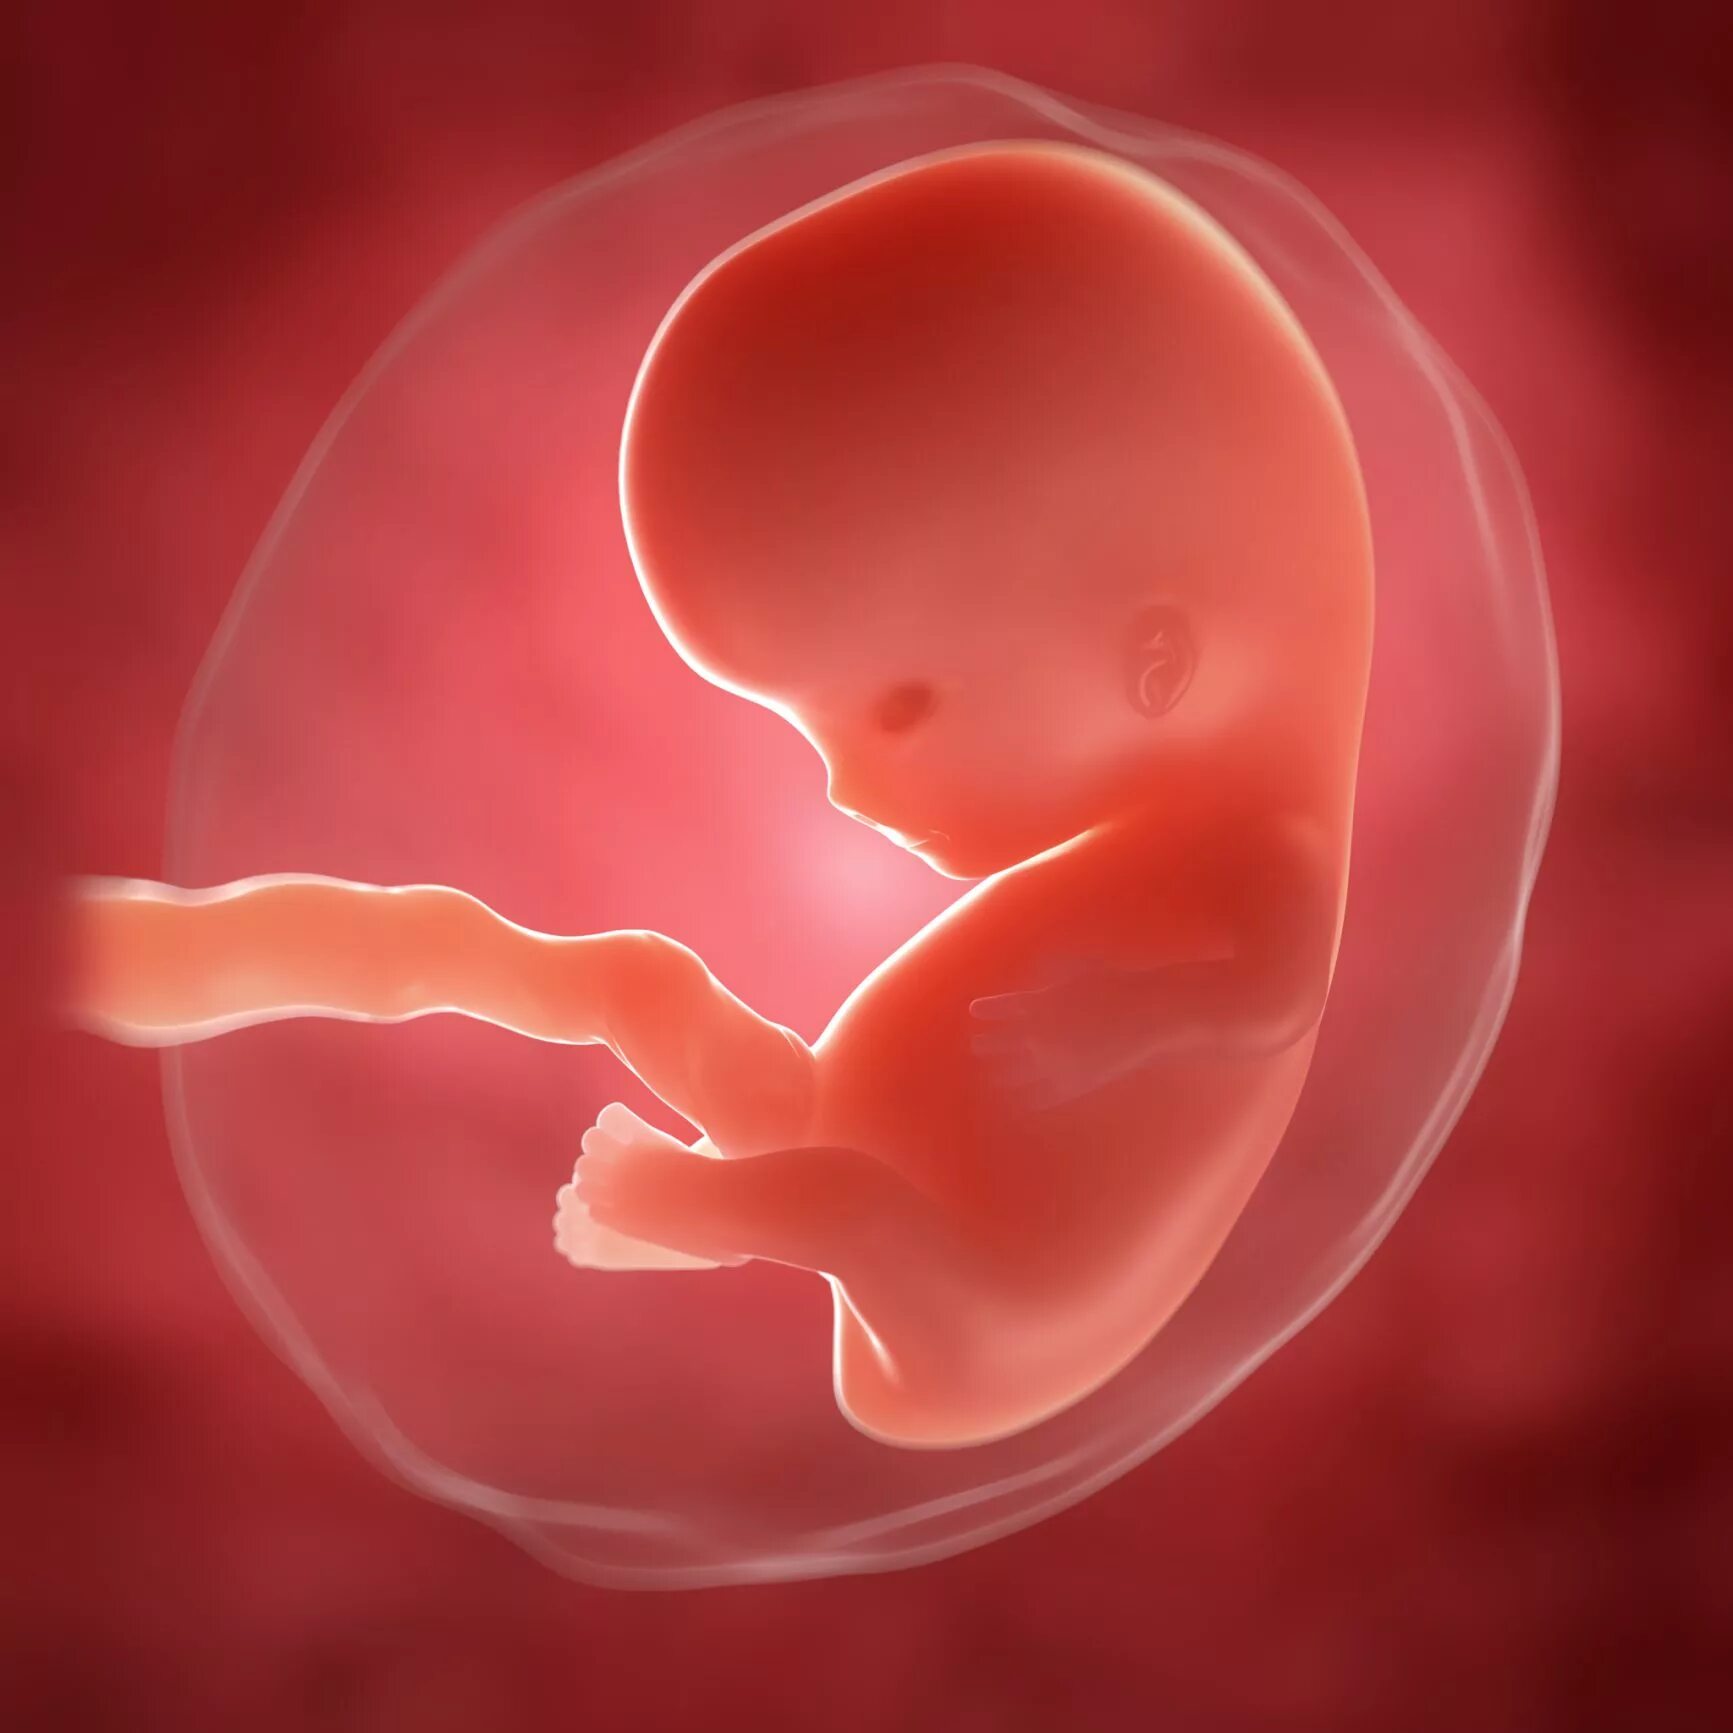

7 недель какой ребенок